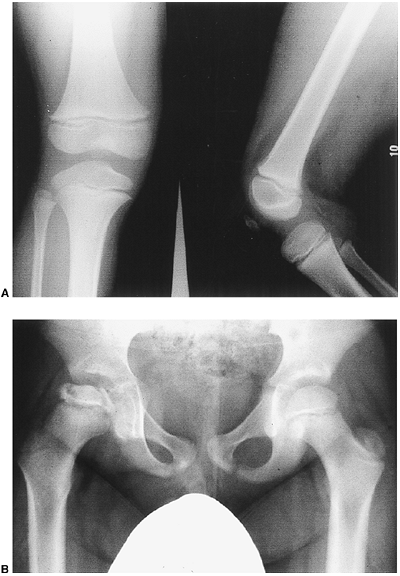

Patients frequently have younger skeletal age than cohorts. Frequently,

the disease presents as a painless limp (Fig. 5-2). -

Figure 5-2. A 6-year-old boy with a 1- to 2-month history of limping and right knee pain. A: Radiographs of the knee are normal. B: An AP pelvis radiograph reveals changes in the right hip consistent with Legg-Calvé-Perthes disease.P.80P.81The hallmarks of treatment consist of:-